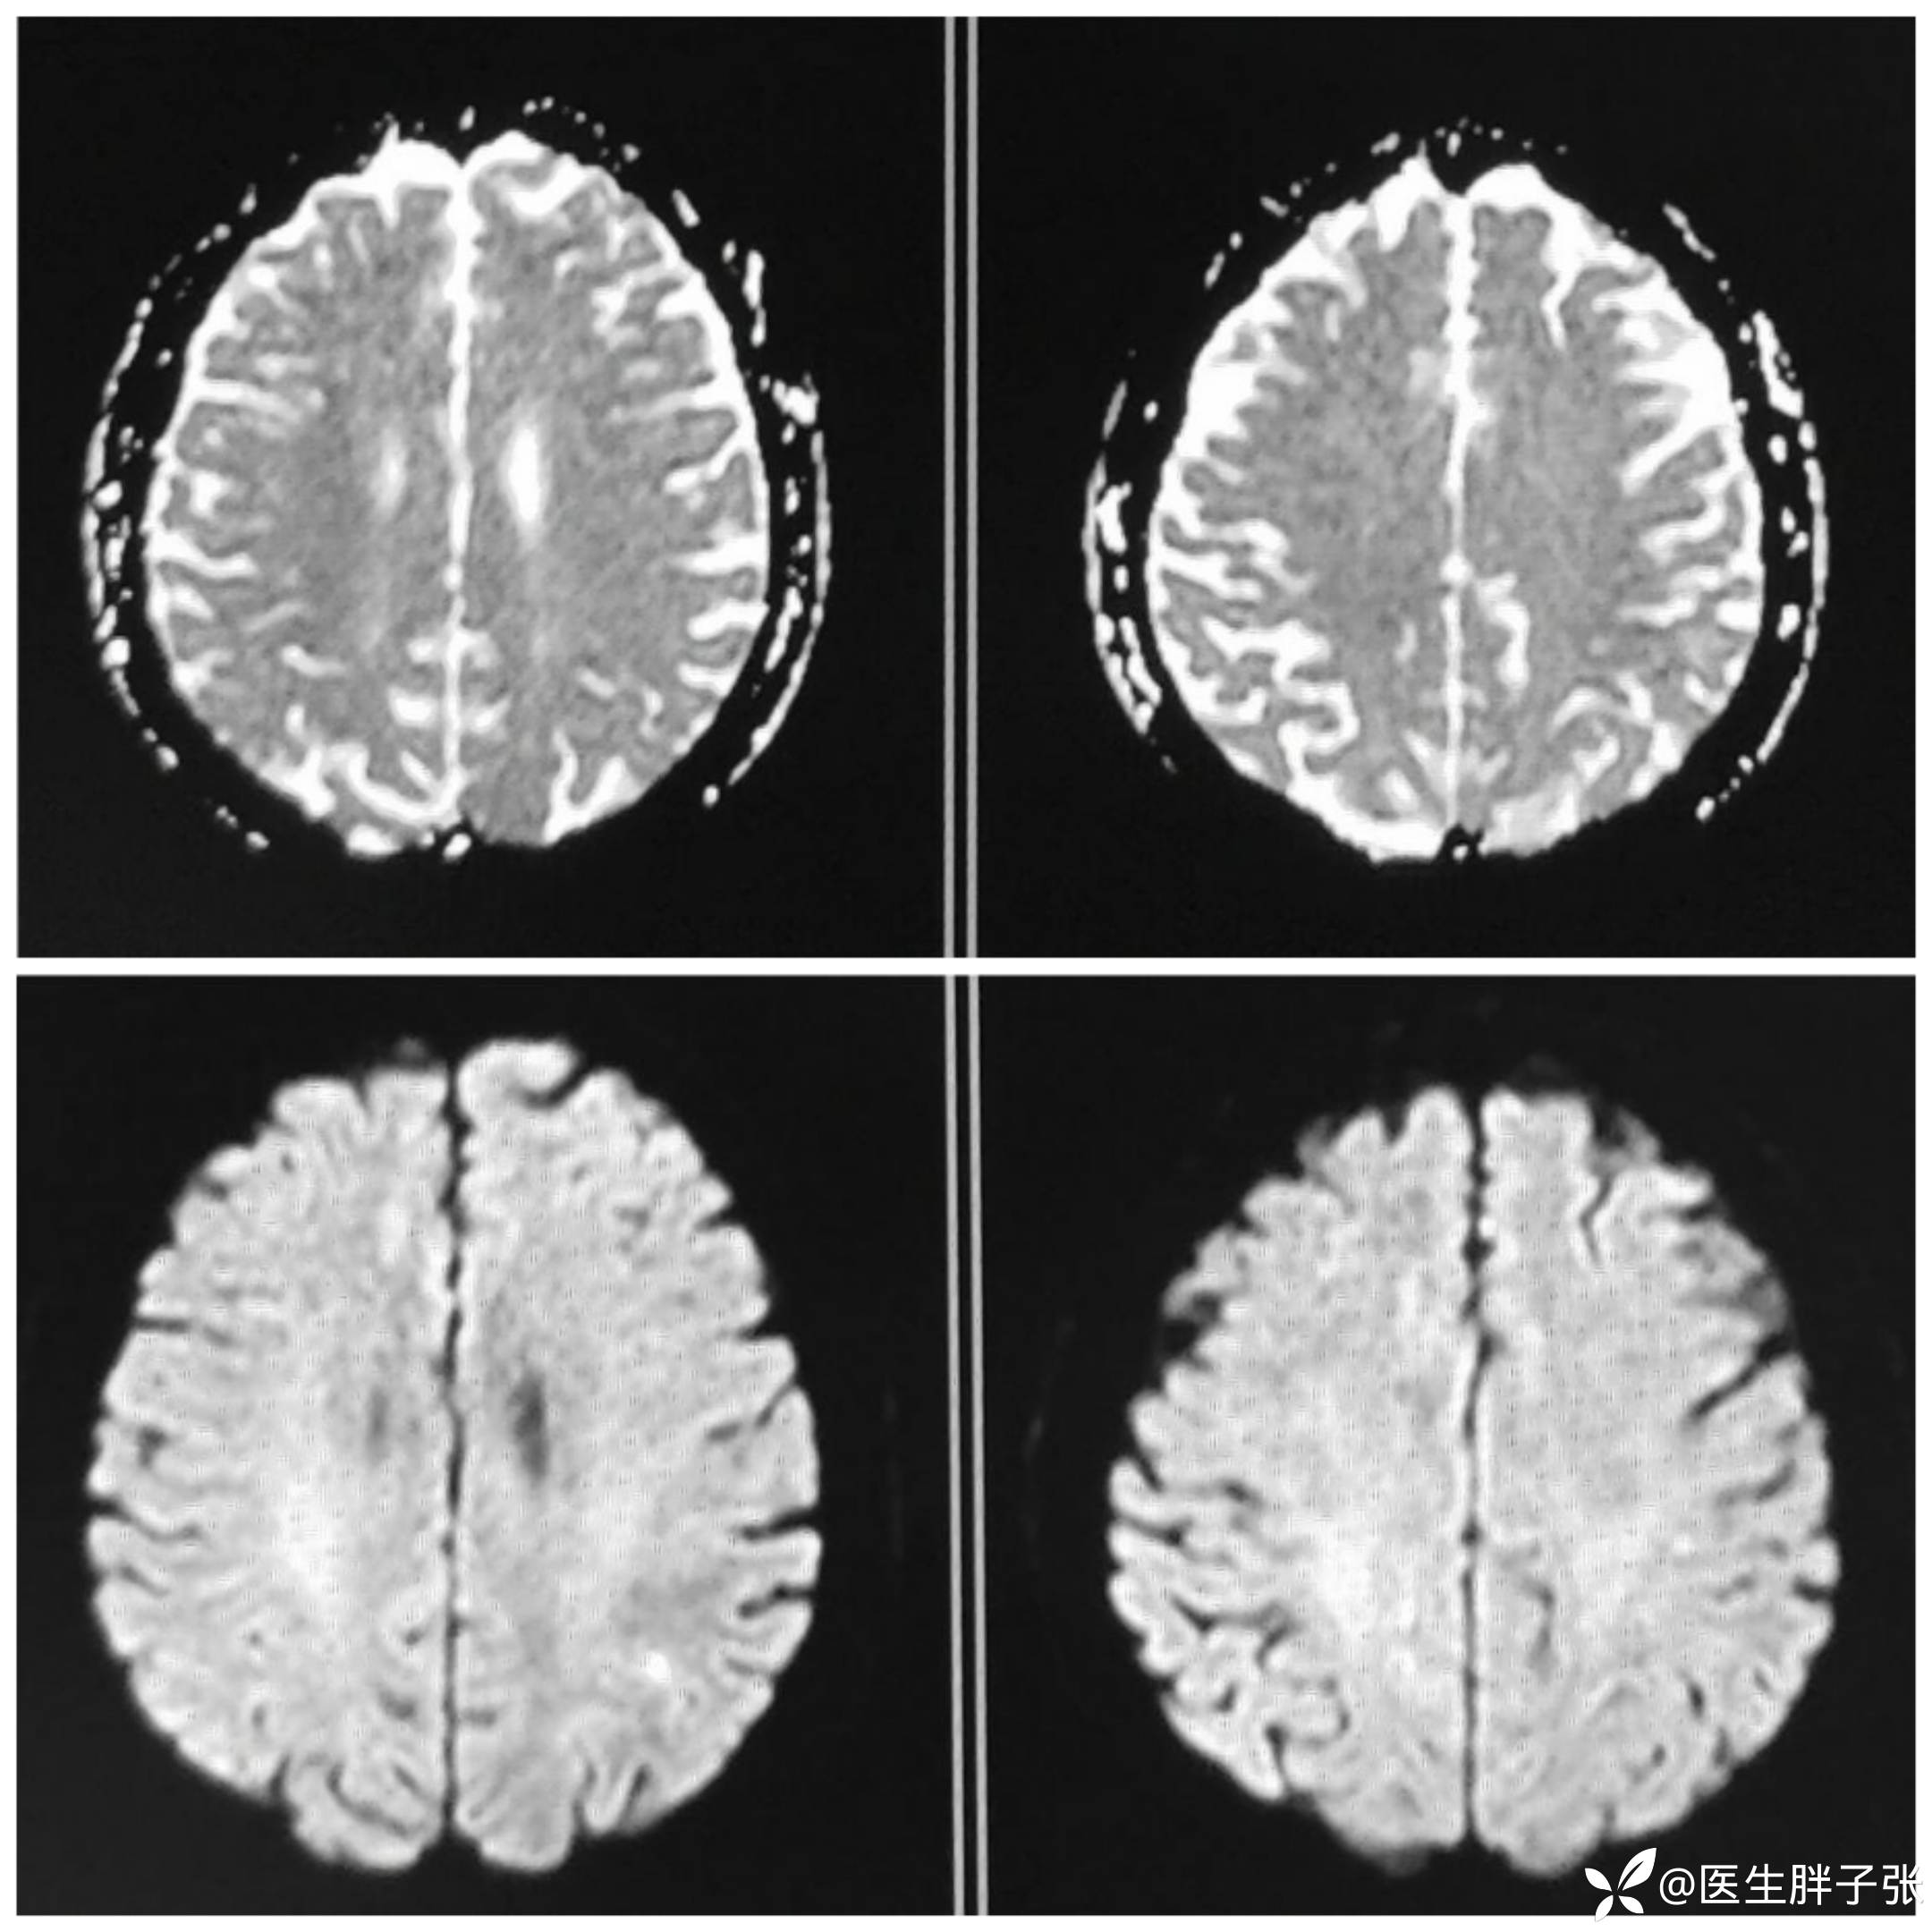

颅脑MR回报左侧顶叶新近梗死灶;多发腔隙性脑梗死及缺血灶;MRA未见异常。

再次查看核磁,考虑患者左侧顶枕叶及右侧枕叶脑组织存在混杂信号。